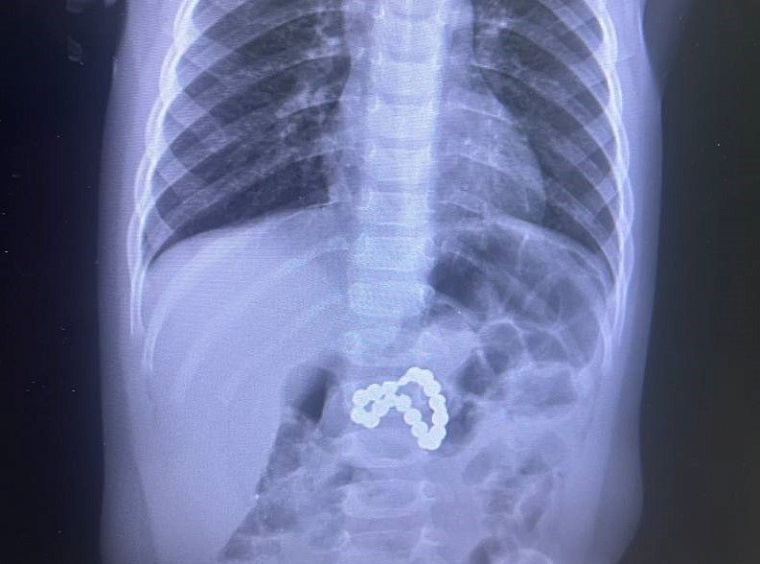

Сургутские врачи спасли проглотившую магниты девочку

Ребенок чуть не лишился желудка.

В Центре охраны материнства и детства в Сургуте смогли спасти ребенка, который серьезно пострадал от проглоченных переносных магнитов. Девочку в крайне тяжелом состоянии экстренно доставили в больницу, сообщает телеканал «Мегаполис».

«Предметы фактически разорвали желудок и кишечник. Медикам пришлось в срочном порядке делать эндоскопию, сшивать внутренние органы и переливать кровь», — рассказало подробности издание. Спасением девочки сутки занималась бригада хирургов, реаниматологов, эндоскопистов и медицинских сестер.

Фото: Сургутский центр охраны материнства и детства